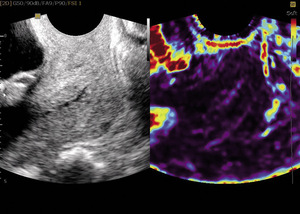

Pomysłem ośrodka gdańskiego było zastosowanie tej samej metody do oceny elastyczności szyjki macicy ciężarnej jako jednego z wykładników zbliżającego się porodu. Zastosowaliśmy badanie sondą pochwową w aparatach Samsung-Medison V10 i V20 z oprogramowaniem Elastoscan™. Uzyskane obrazy prezentują elastyczność tkanek w skali względnej. Przy zastosowaniu skali kolorów tęczy nr 2 tkanki najtwardsze obrazowane są jako fioletowe, mniej elastyczne jako niebieskie oraz dalej jako zielone i żółte, aby w kolorze czerwonym uwidocznić tkanki najbardziej podatne. Aby uzyskać obraz elastograficzny, potrzebny jest ruch. W elastografii położniczej ruch otaczających tkanek i naczyń krwionośnych szyjki jest wystarczający, aby uzyskać właściwe zobrazowanie.7-13

Na potrzeby analizy uzyskanych wyników w Klinice Położnictwa w Gdańsku opracowany został przez dr hab. med. Małgorzatę Świątkowską-Freund tzw. indeks elastografii (elastography index, EI), następnie opublikowany i zastosowany w naszych badaniach. Ta prosta pięciopunktowa skala (od 0 do 4 pkt) okazała się łatwa i skuteczna w zastosowaniu klinicznym.11,12